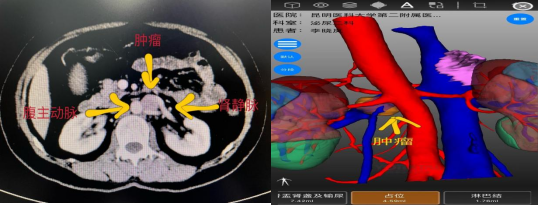

术前影像学检查

该患者既往行左肾上腺解剖性切除术,本次体检发现左侧腹膜后占位性病变,发现后患者在家人的陪伴下慕名前来亚洲色吧 泌尿外科二病区杨德林教授门诊就诊。患者入院后,杨德林主任团队对其病情进行详细研判后发现,该占位性病变位置非常特殊,位于腹主动脉、左肾静脉、左肾动脉之间,与左肾静脉关系尤为密切,肿瘤位置较深,周围血管关系复杂,手术难度极大,术中稍不注意就可能导致周围血管的损伤从而影响重要器官的功能。若从肿瘤位置观察经腹膜后可能相对更好显露,但患者既往有手术病史,经腹膜后途径可能粘连严重。因此,经过综合考量后,团队决定积极做术前准备,手术采用机器人辅助下经腹入路。